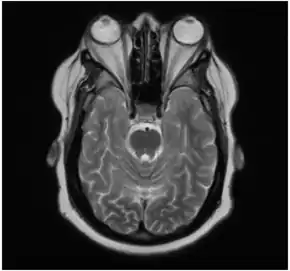

In the case of Graves' disease, the displacement of the eye results from abnormal connective tissue deposition in the orbit and extraocular muscles, which can be visualized by CT or MRI.[1]